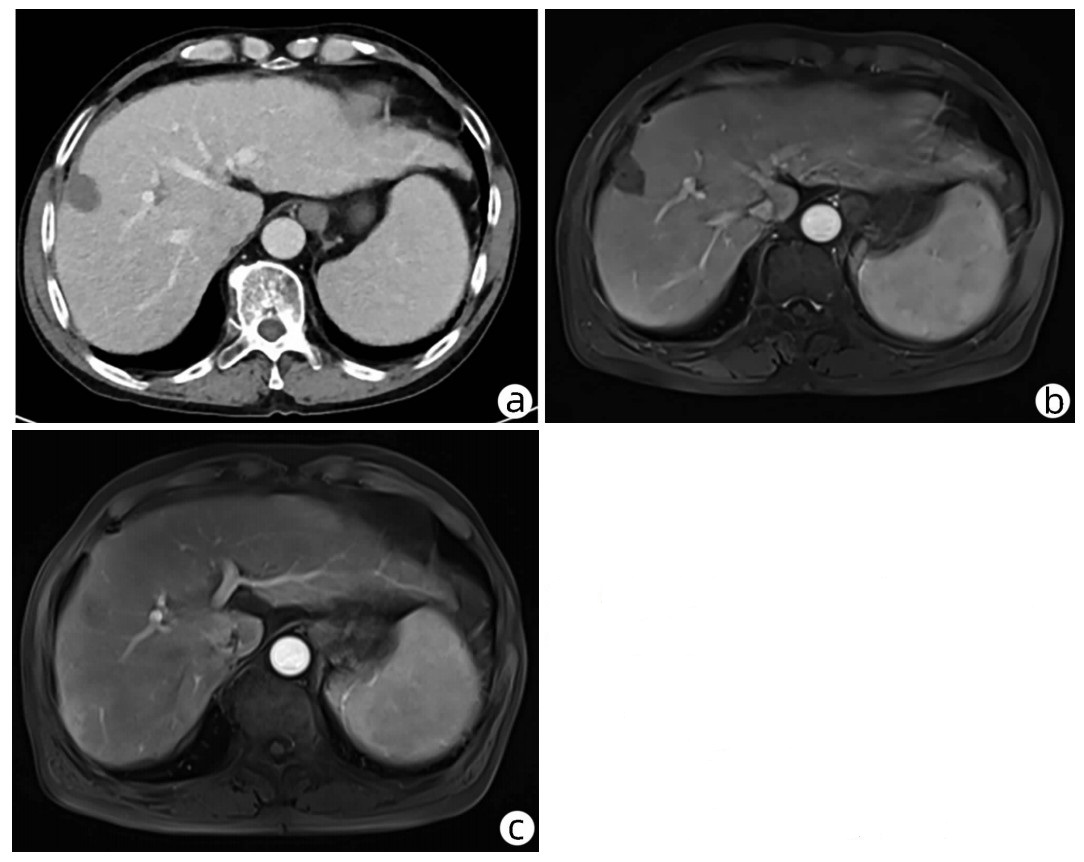

Hepatocellular carcinoma with bile duct tumor thrombus: A case report

Renjie LU, Fangfang SUN, Jie DU, Lirong ZHAO

2022, 38(8): 1872-1874. DOI: 10.3969/j.issn.1001-5256.2022.08.028

Abstract(762) HTML (437) PDF (3665KB)(68)

Abstract: